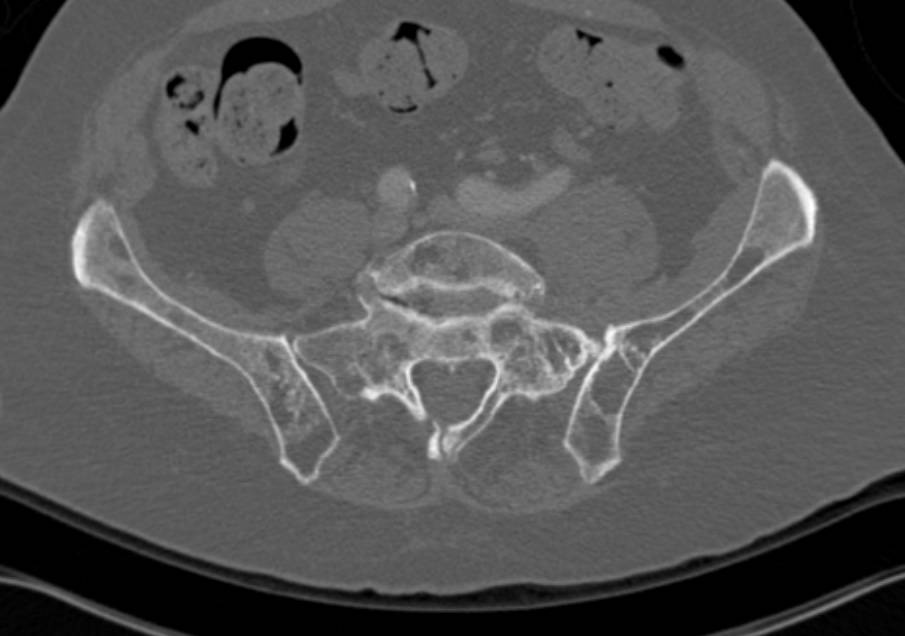

Right Hip Dislocation in 3D VRT